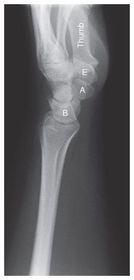

Lateral Wrist

Lateromedial